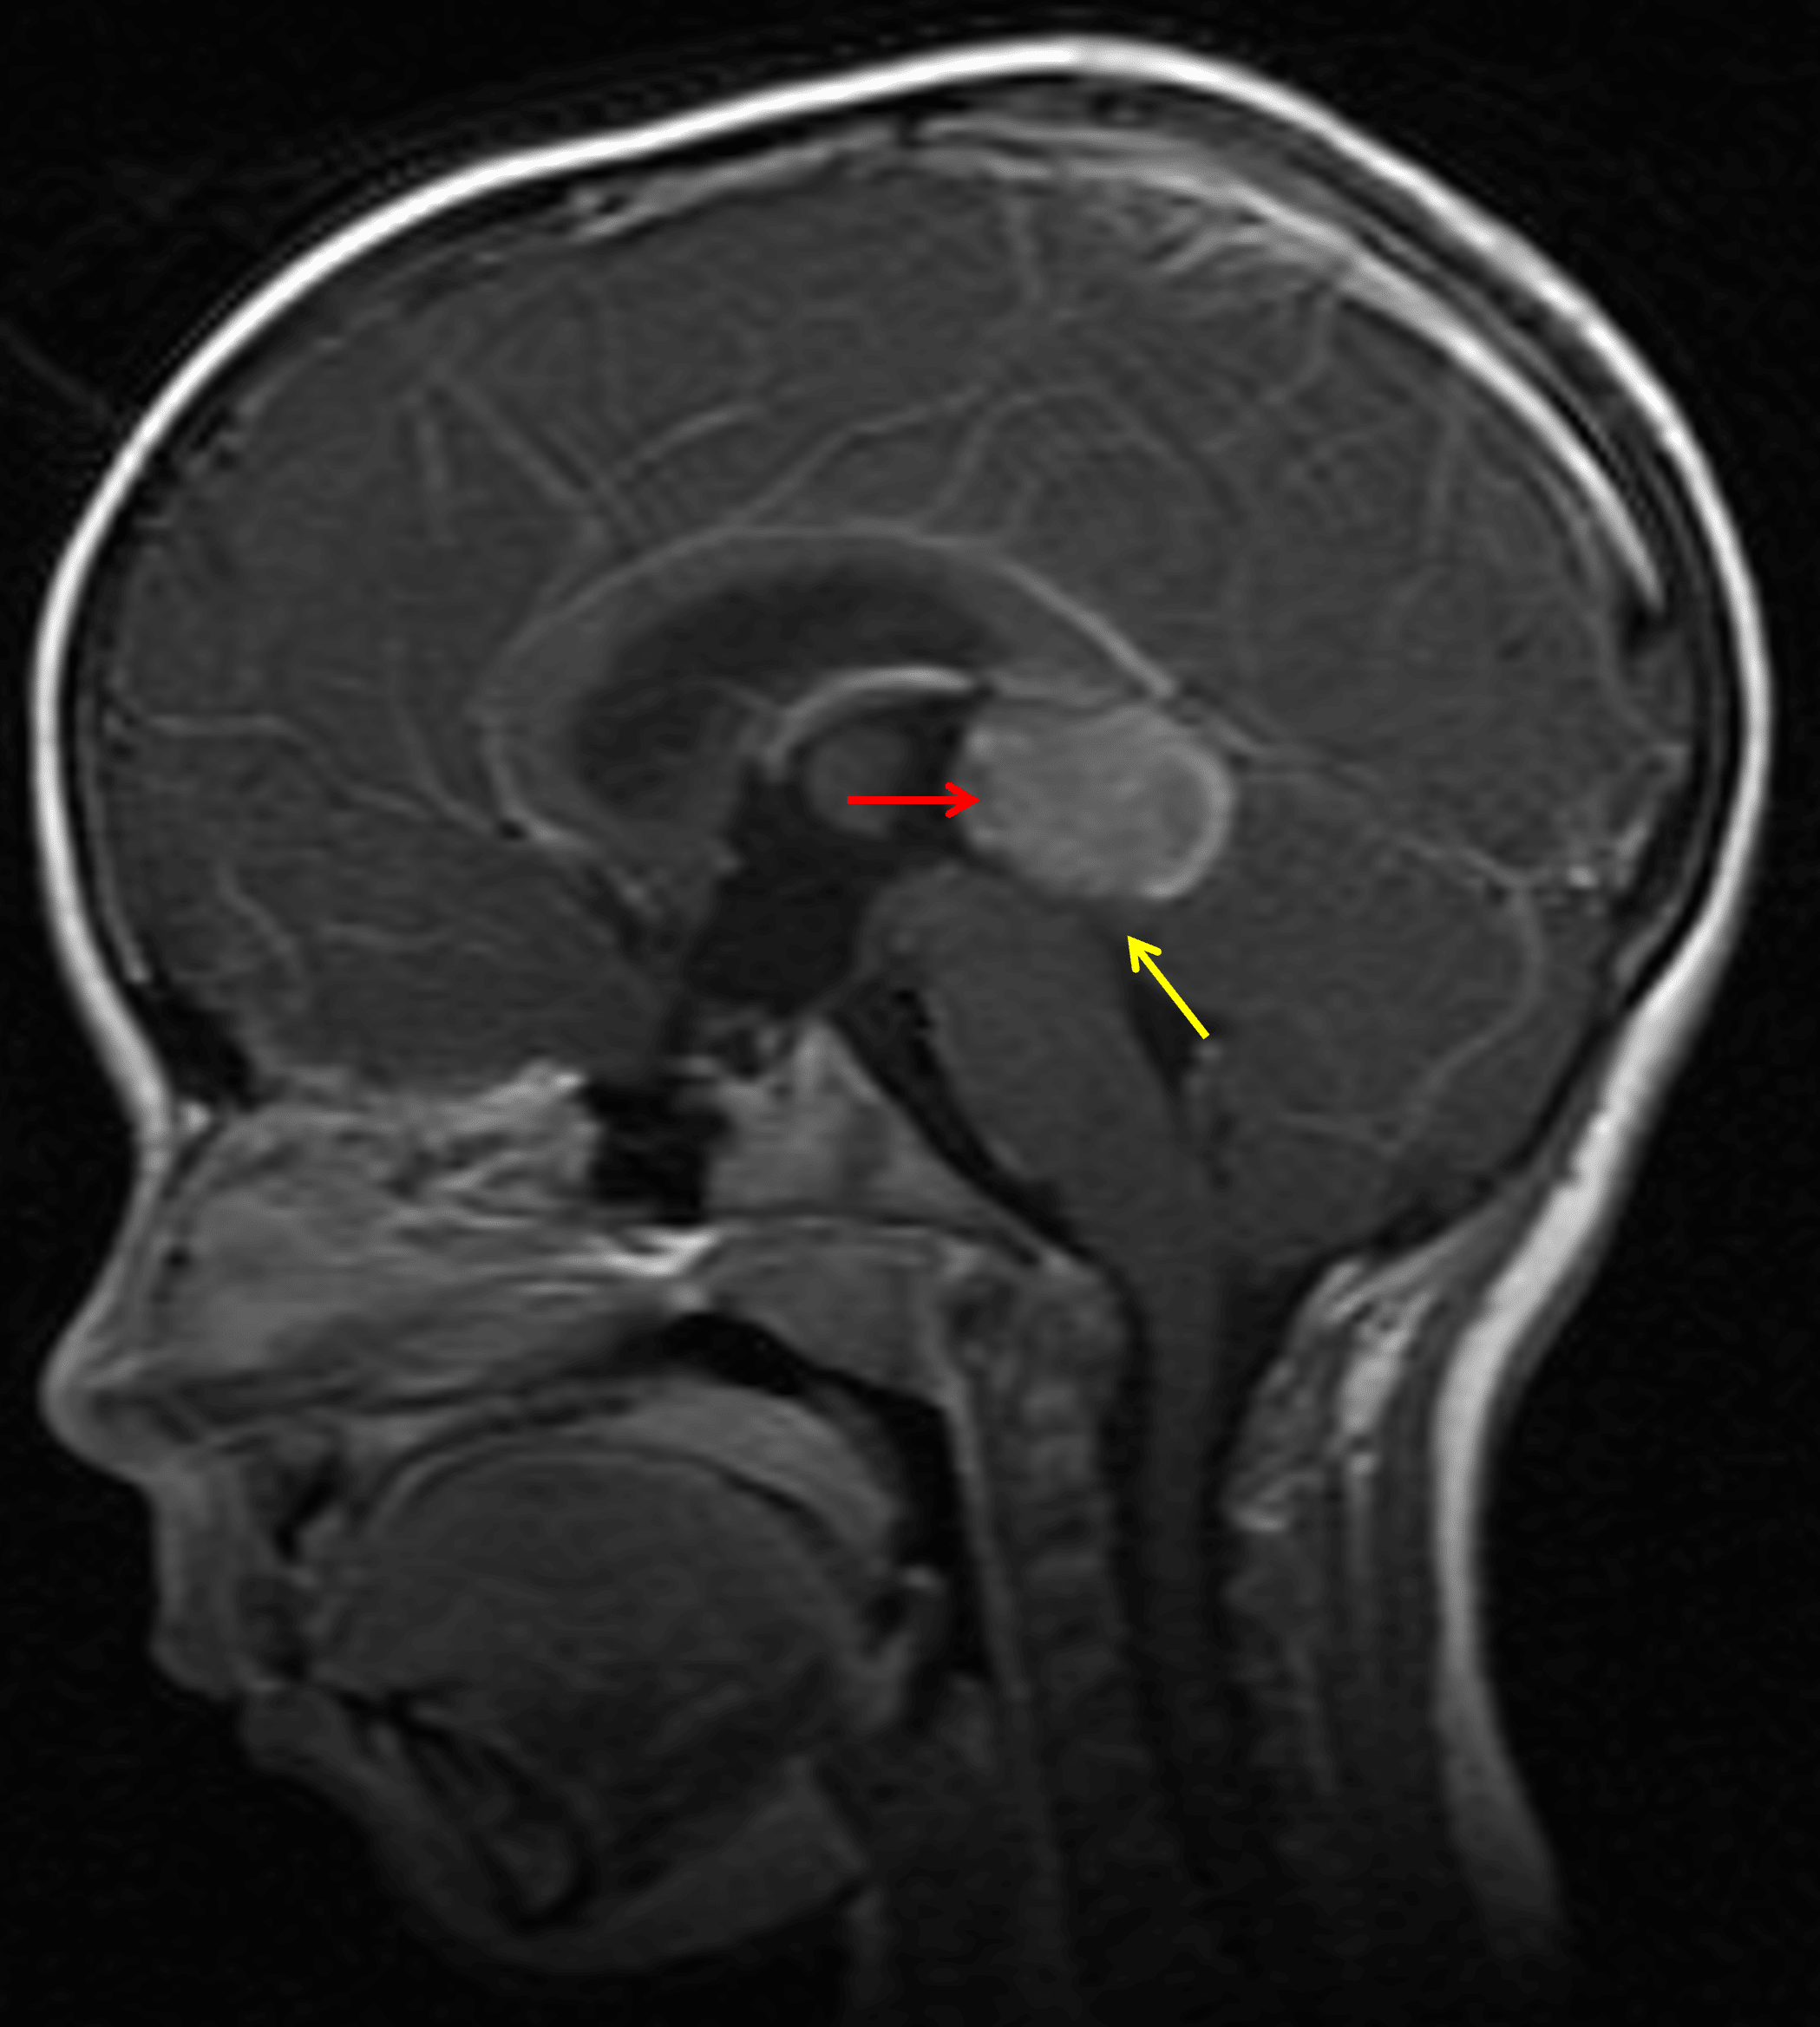

- Avidly enhancing pineal region mass measuring 3 x 2.8 x 2 cm

- Downward mass effect on the tectum with crowding of the cerebral aqueduct and obstructive hydrocephalus involving the lateral and third ventricles

Enhancing pineal region mass (red arrow) with downward mass effect on the tectum (yellow arrow).

Pineoblastoma